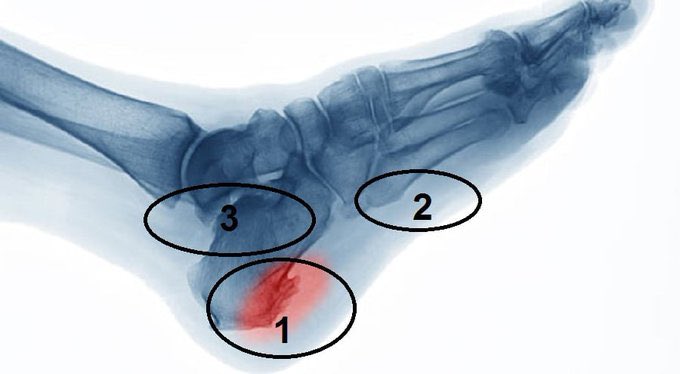

مسمار القدم : هو عبارة عن بروز لحمي أو نسيج يظهر على القدم، سبب ظهورها ضغط الجلد والعظام ضد الحذاء،وله الكثير من المُسميات الأخرى كالكالو أو عين السمكة أو مسمار الكيف،  وهذا المرض من الأمراض التي تُصيب الجلد بشكل مُباشر.

يتكون مسمار القدم : من خلايا ميتة تتراكم على سطح الجلد وقد يبدو المسمار للناظر سطحياً إلّا أنّه عادة يكون على شكل قمع عميق في الجلد يحدث ألماً إذا ضغط عليه ..

- التهاب وتهييج اللفافة الأخمصية للقدم (مسمار القدم).